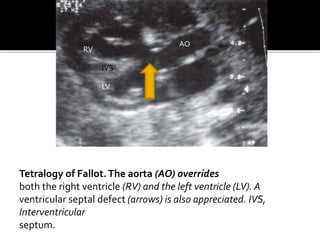

Tetralogy of Fallot.The aorta (AO) overrides

both the right ventricle (RV) and the left ventricle (LV). A

ventricular septal defect (arrows) is also appreciated. IVS,

Interventricular

septum.

Tetralogy of Fallot.Theaorta (AO) overrides both the right ventricle (RV) and the left ventricle (LV). A ventricular septal defect (arrows) is also appreciated. IVS, Interventricular septum. RV LV IVS AO